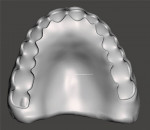

The final design data from the scanned impressions and try-ins were merged and the arches were aligned in the CAD software. Virtual models of the maxillary and mandibular arches were then created (Figure 8 and Figure 9). The virtual models were oriented in the proper VDO and CO positions as established by the scanned try-ins and bite registrations to allow design of the final prosthetics in the optimal orientations (Figure 10). The initial denture tooth positions from the try-in were adapted to the master impression surfaces and final tooth positions that were established during the clinical try-in and bite registration, which were incorporated into the digital design (Figure 11 through Figure 13).